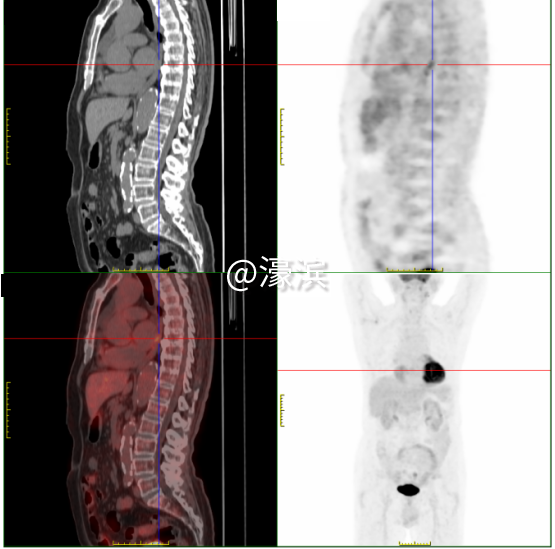

①食管癌精准定位 发现食管下段1.3cm管壁增厚伴FDG代谢增高(SUVmax 3.1),与病理结果高度吻合,为后续手术或放疗提供精准靶区定位。 ②全身隐匿病灶"无处遁形" 鉴别颈部炎性淋巴结(SUVmax 4.2)与转移灶,避免过度治疗;发现双肾囊肿(最大3.6cm)、肝囊肿等良性病变,完善全身健康评估;识别牙槽根周炎症(SUVmax 10.9)、上颌窦炎等感染灶,指导抗炎治疗。 ③全身健康"全景扫描" 同步检出肺气肿、冠脉钙化、前列腺增生伴钙化等退行性病变,精准锁定多处微小病灶,为多学科诊疗提供完整数据支持。 "对于SUVmax<2.5的病灶,如本例患者的食管癌灶,我们也能通过双能谱CT物质分离技术,识别早期癌变的特征性脂质成分变化。"瑞慈医院医学影像科核医学组主任夏淦林提到,"PET-CT不是简单的影像设备,而是现代精准医疗的决策中枢,精准捕捉到<1cm的微小病灶。" 选择瑞慈PET-CT的四大理由?  (一)美国GE进口超高清设备:高灵敏度、高清晰度、高分辨率、高扫描速度、高精准定量测量 (二)专业影像科团队:从业20余年的“南通PET-CT第一人”领衔解读诊断报告 (三)检查快速高效:提前一天预约即可检查,检查后最早当天下午出报告,最晚第二天上午出报告。 (四)星级检查环境:独立贵宾休息室,隐私零干扰、全流程单向通行,动线设计更科学。 PET-CT主要解决哪些问题? PET-CT在肿瘤方面的应用占其床应用的90%以上。 主要适应症如下: 协助诊断 ·对肿瘤高危人群,早期发现或排除肿瘤; ·对肿瘤标志物高或副肿瘤综合征患者,寻找肿瘤病灶所在; ·对已发现可疑病变者,鉴别良、恶性; ·对可疑肿痛患者,指导选择活检部位; ·对已发现肿瘤转移者,寻找原发灶。 指导治疗 ·对恶性肿瘤患者,进行更准确分期,全面了解全身病变情况; ·肿瘤恶性程度分级和预后判断; ·指导放疗计划靶区的设定。 疗效评估和复发监测 ·肿瘤治疗效果的评估; ·肿瘤残存病灶与坏死、纤维化组织的鉴别; ·肿瘤治疗后标志物仍高或重新升高,寻找残存、复发或转移病灶; ·肿瘤复发的监测。